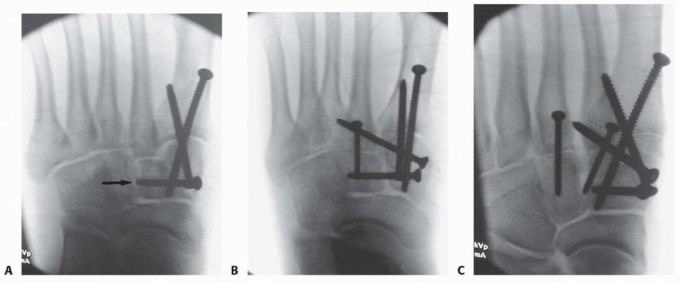

3. ## Provisional Reduction and Definitive Stabilization

First Tarsometatarsal Joint

The provisional reduction begins medially at the first tarsometatarsal joint if injured. Although the exact reduction maneuver may vary depending on the injury pattern, the first metatarsal is typically supinated (externally rotated) relative to the medial cuneiform.

Correction of this rotational deformity is crucial in restoring the medial column and the weight-bearing

function of the first ray. The reduction of the remaining midfoot joints depends on an anatomic reduction of the first tarsometatarsal joint.

The provisional reduction is held with a 2.0-mm Kirschner wire and confirmed under fluoroscopy (

TECH FIG 3A

).

TECH FIG 3 • Reduction and stabilization of first tarsometatarsal joint. A. Provisional reduction. B. Distal to proximal screw. C. Proximal to distal screw. D. Long bicortical trajectory of screws for enhanced stability. Definitive stabilization is then obtained at the first tarsometatarsal joint with 3.5-mm solid cortical position screws (

TECH FIG 3B-D

The first screw is placed from distal to proximal, starting at the dorsal crest and distal to the metaphyseal-diaphyseal junction, and is angled toward the plantar-proximal cortex of the medial cuneiform; this screw is generally 45 to 50 mm long.

A second screw is placed from proximal to distal starting at the edge of the naviculocuneiform joint and similarly angled to exit at the plantar cortex distal to the metaphyseal-diaphyseal junction. This screw typically measures 40 to 45 mm.

In a primary arthrodesis, these screws are placed in lag fashion.

For larger patients, 4.0-mm cortical screws may be used for further stability.

TECH FIG 4 • Reduction and stabilization of Lisfranc joint. A. Pointed reduction forceps. B. Supplemental Kirschner wire. C. Screw fixation. Trajectory of screw mirrors the normal path of ligamentous structures. Intercuneiform joint was previously reduced and stabilized as initial step.Lisfranc Joint A pointed reduction forceps is then placed from the medial cuneiform to the lateral border of the second metatarsal to anatomically reduce the so-called Lisfranc joint; care is taken to ensure accurate dorsal-plantar alignment of the second tarsometatarsal joint.

The reduction is confirmed under fluoroscopy, and a 2.0-mm Kirschner wire that mirrors the intended path of the screw is placed to provide further rotational control (

TECH FIG 4A,B

There is typically a distinct cortical “shelf” on the medial cuneiform that provides an excellent buttress for screw purchase.

A 3.5-mm cortical screw is placed through a stab incision overlying this cortical shelf medially, angling toward the proximal metaphysis of the second metatarsal; for a primary arthrodesis, this screw is placed in lag fashion (

TECH FIG 4C

Other Joints

If the intercuneiform joint is involved, it is first reduced and stabilized before stabilizing the Lisfranc joint (

TECH FIG 5A

). Alternatively, this joint may also be reduced and stabilized before stabilizing the first tarsometatarsal joint.

A 3.5-mm cortical screw is again used, coursing parallel to the plane of the naviculocuneiform joint. It is placed in lag fashion for a primary arthrodesis.

Care is taken not to violate the articulation between the middle and lateral cuneiform.

The second tarsometatarsal joint is then provisionally reduced and provisionally stabilized with a 1.6-mm Kirschner wire.

Definitive fixation is obtained with a countersunk 2.7-mm cortical screw from distal to proximal; it is placed in lag fashion for a primary arthrodesis (

TECH FIG 5B

--- TECH FIG 5 • A. Reduction and stabilization of intercuneiform joint. B. Reduction and stabilization of second tarsometatarsal joint. C. Reduction and stabilization of third tarsometatarsal joint.

TECH FIG 5 •

(continued)

D. Comminuted second metatarsal and second and third tarsometatarsal joints. E,F. Second and third metatarsals and segmental fourth metatarsal in a different patient. G. Kirschner wire fixation of fourth and fifth tarsometatarsal joints.

H.

Reduction and stabilization of cuboid through separate proximal-lateral incision.

I.

Fluoroscopic image.

The third tarsometatarsal joint is reduced and stabilized in identical fashion (

TECH FIG 5C

For a metatarsal base fracture or fracture-dislocation pattern precluding transarticular fixation, bridge plate fixation may be required.

We prefer a low-profile (2.0 or 2.4 mm) reconstruction plate and 2.4-mm cortical screws (

TECH FIG 5D-F

The fourth and fifth tarsometatarsal joints are then reduced and definitively stabilized with 1.6-mm Kirschner wires.

Because the intermetatarsal ligaments between the third, fourth, and fifth metatarsals are often preserved, these joints may anatomically reduce indirectly, thereby allowing percutaneous stabilization.

The Kirschner wires are contoured and buried beneath the skin layer through separate stab incisions, which facilitates removal at 6 weeks postoperatively, either in the office under local anesthesia or in the operating room under sedation (

TECH FIG 5G

For a cuboid fracture, the cuboid is reduced and definitively stabilized to ensure restoration of lateral column length before stabilizing the fourth and fifth tarsometatarsal joints; by definition, this is then an open reduction (

TECH FIG 5H

Final fluoroscopic images are obtained, confirming articular reduction and implant placement (

TECH FIG 5I